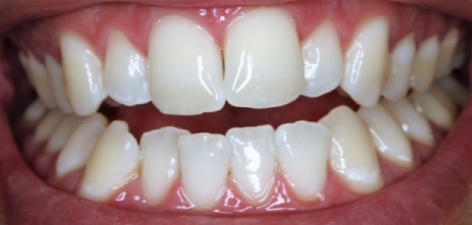

En la fotografía inicial se aprecian piezas deterioradas y con alteraciones estéticas, mientras que en la imagen final se observa una sonrisa renovada, con coronas que devuelven uniformidad, función y un aspecto natural.